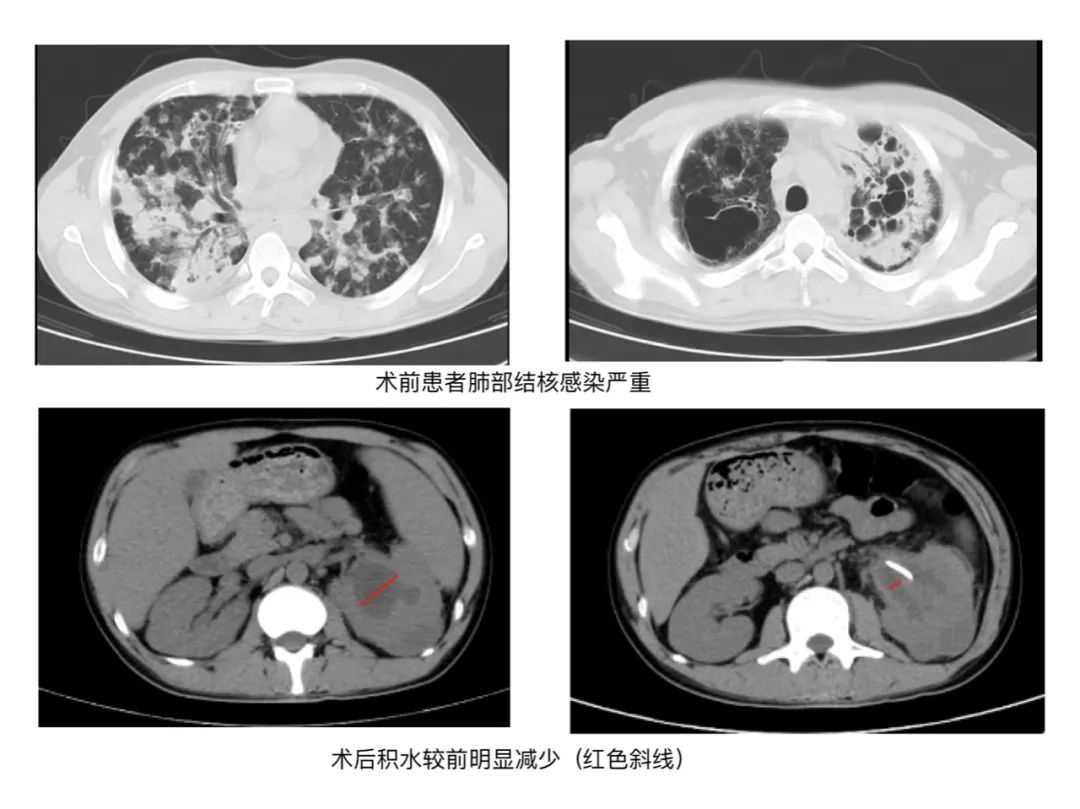

据了解,该患者患上肺结核后,由于没有及时的治疗,到院治疗时结核杆菌已播散到全身各处,并导致了左肾及输尿管异常改变,左肾积水、输尿管扩张,结合病史考虑为泌尿系结核。

泌尿外科专家仔细讨论患者的病情后,决定给予患者行左侧输尿管支架置入术。由于泌尿系结核有着瘢痕挛缩、干酪样坏死的特性,术中有可能寻找输尿管口困难、输尿管狭窄,因此备选左侧经皮肾造瘘术。

术后,患者来院时的腰疼及发热症状消失。复查后,CT提示积水已经有了明显减少。在经过抗感染治疗后,患者顺利康复出院。